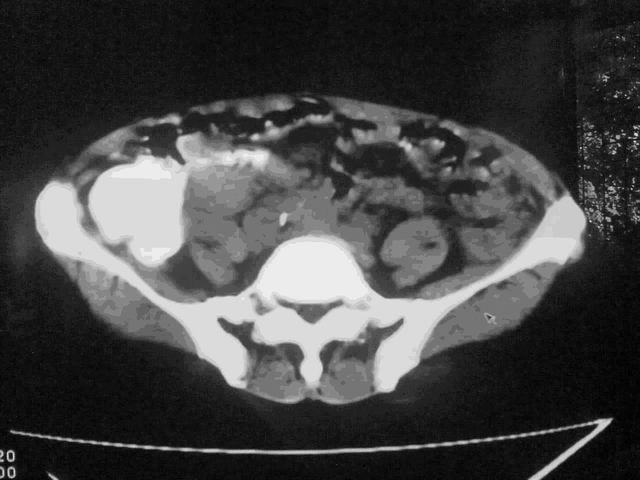

我这个考考大家眼力,看看是升结肠ca还是降结肠ca

结肠占位并肝及腹膜后淋巴结转移。

明确考眼力!考虑降结肠癌伴肝转移可能性。

伪影太多,考虑降结肠癌伴肝转移,胆囊炎。